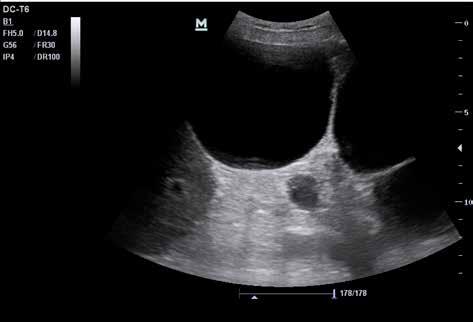

4.1 Freie abdominelle Flüssigkeit

Von freier abdomineller Flüssigkeit (FAF) spricht man, wenn sich im Ultraschall echofreies Material im Bauchraum (intraperitoneal) findet. Normalerweise ist in der Bauchhöhle keine Flüssigkeit zu erwarten, d. h. der sonografische Nachweis von freier intraabdominel ler Flüssigkeit ist immer als pathologisch anzusehen. Freie Flüssigkeit muss aber nicht in jedem Fall Blut sein. Freie Flüssigkeit aufgrund einer anderen Vorerkrankung wird auch als „Aszites“ bezeichnet. Aszites ist Flüssigkeit, die entweder aktiv in die Bauchhöhle sezer niert wird oder passiv aus den Gefäßwänden austritt.

Die Unterscheidung zwischen einer Blutung in die Bauchhöhle und einer anderen Ursa che der FAF ist präklinisch oft nur anhand der Wahrscheinlichkeit möglich. Für eine end gültige Diagnosesicherung ist eine Punktion notwendig. Oft hilft aber der gesunde Men schenverstand – bei einem akut außerorts mit dem Motorrad verunglückten jungen Mann mit freier abdomineller Flüssigkeit ist ein Aszites durch Leberzirrhose nicht unbedingt die wahrscheinlichste Diagnose.

Zunächst sammelt sich mögliche freie Flüssigkeit an drei typischen präformierten Stel len im Bauchraum und kann hier sonografisch dargestellt werden. Dies sind der MorisonPouch, der Koller-Pouch und der Douglas-Raum (von engl. „Pouch“ für „Beutel“, Abb. 34 –36).

Der Morison-Pouch ist eine Aussackung des Peritoneums zwischen Leberunterrand und rechter Niere. Dem entspricht auf der Gegenseite der Koller-Pouch zwischen Milz und linker Niere. Der Douglas-Raum befindet sich dorsal hinter der Harnblase und zieht bis ins kleine Becken.

Sonografie bei freier abdomineller Flüssigkeit

In Anbetracht der Umgebungsumstände und der Notfallsituation wird ein Patient mit möglicher freier abdomineller Flüssigkeit in Rückenlage untersucht werden. Zur Abdo mensonografie wird der Curved-Array-Schallkopf verwendet.

Je nach Menge der freien Flüssigkeit ist in den beschriebenen Räumen ggf. nur eine schmale echofreie Lamelle zu erkennen, bei erheblichen Mengen freier Flüssigkeit ist diese aber auch im ganzen Bauchraum sichtbar. So sieht man bei Patienten mit fortge schrittener Leberzirrhose oftmals im ganzen Bauch nur noch „schwarz“, und darin einge bettet die parenchymatösen Oberbauchorgane ebenso wie den Darm.